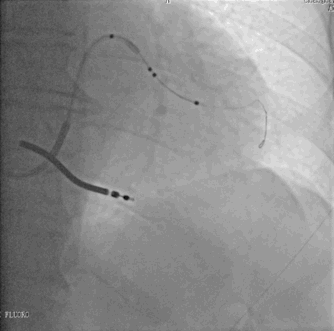

球囊辅助技术的应用

美敦力2.0*15mm球囊前端扩张4ATM引导鞘中鞘进入靶血管中段---优势:

球囊辅助技术

•打圈的导丝

电极无法沿导丝通过!!!!

•导丝通过后扭曲血管被拉直

•但是四极电极通过仍然困难

•强行推送电极,导丝电极鞘管全部外弹